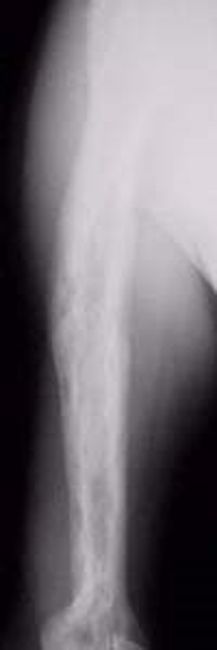

Paget's disease of the humerus

Paget's disease of the humerus (upper arm bone). The diseased bone is dense and wide. It is also patchy from areas of active bone turnover.

In the very early stages of Paget's disease, when there is just overactive absorption of bone occurring, it can look like there is a hole in the bone. Later in the disease process, this darker area can take the shape of a flame or a "V," with denser, thicker bone following behind it.